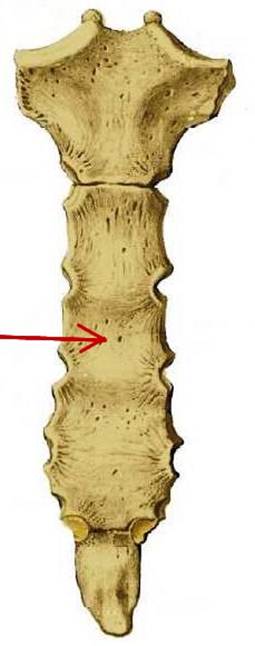

S: Стрелка указывает на corpus sterni (латинский язык).